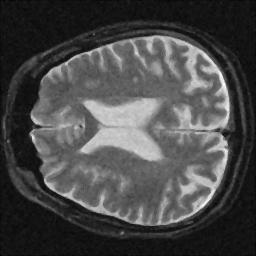

The resolution loss is measured relative to the FWHM of the noisy image, consequently its resolution loss is 0%. Interesting is that the CNR mirrors changes in the SNR, as expected. Also interesting is that the contrast filter reduced the SNR dramatically while actually improving the image resolution. The following images were obtained after filtering:

Wiener Filter